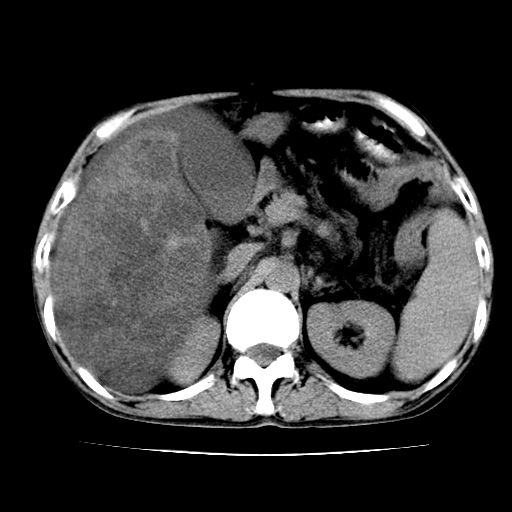

男,55岁,发现“肝硬化”5年,现腰疼、腹胀10余日,巩膜黄染、腹稍胀,肝肋下3指,质硬无压疼,移动性+,血生化:总胆、直胆、间胆均升高。

肝硬化,脾大,腹水

脂肪肝

肝占位待排

肝硬化,脂肪肝,腹水,肝癌

脂肪肝,肝硬化,脾大,腹水。

建议:必要时行ct增强扫描检查。